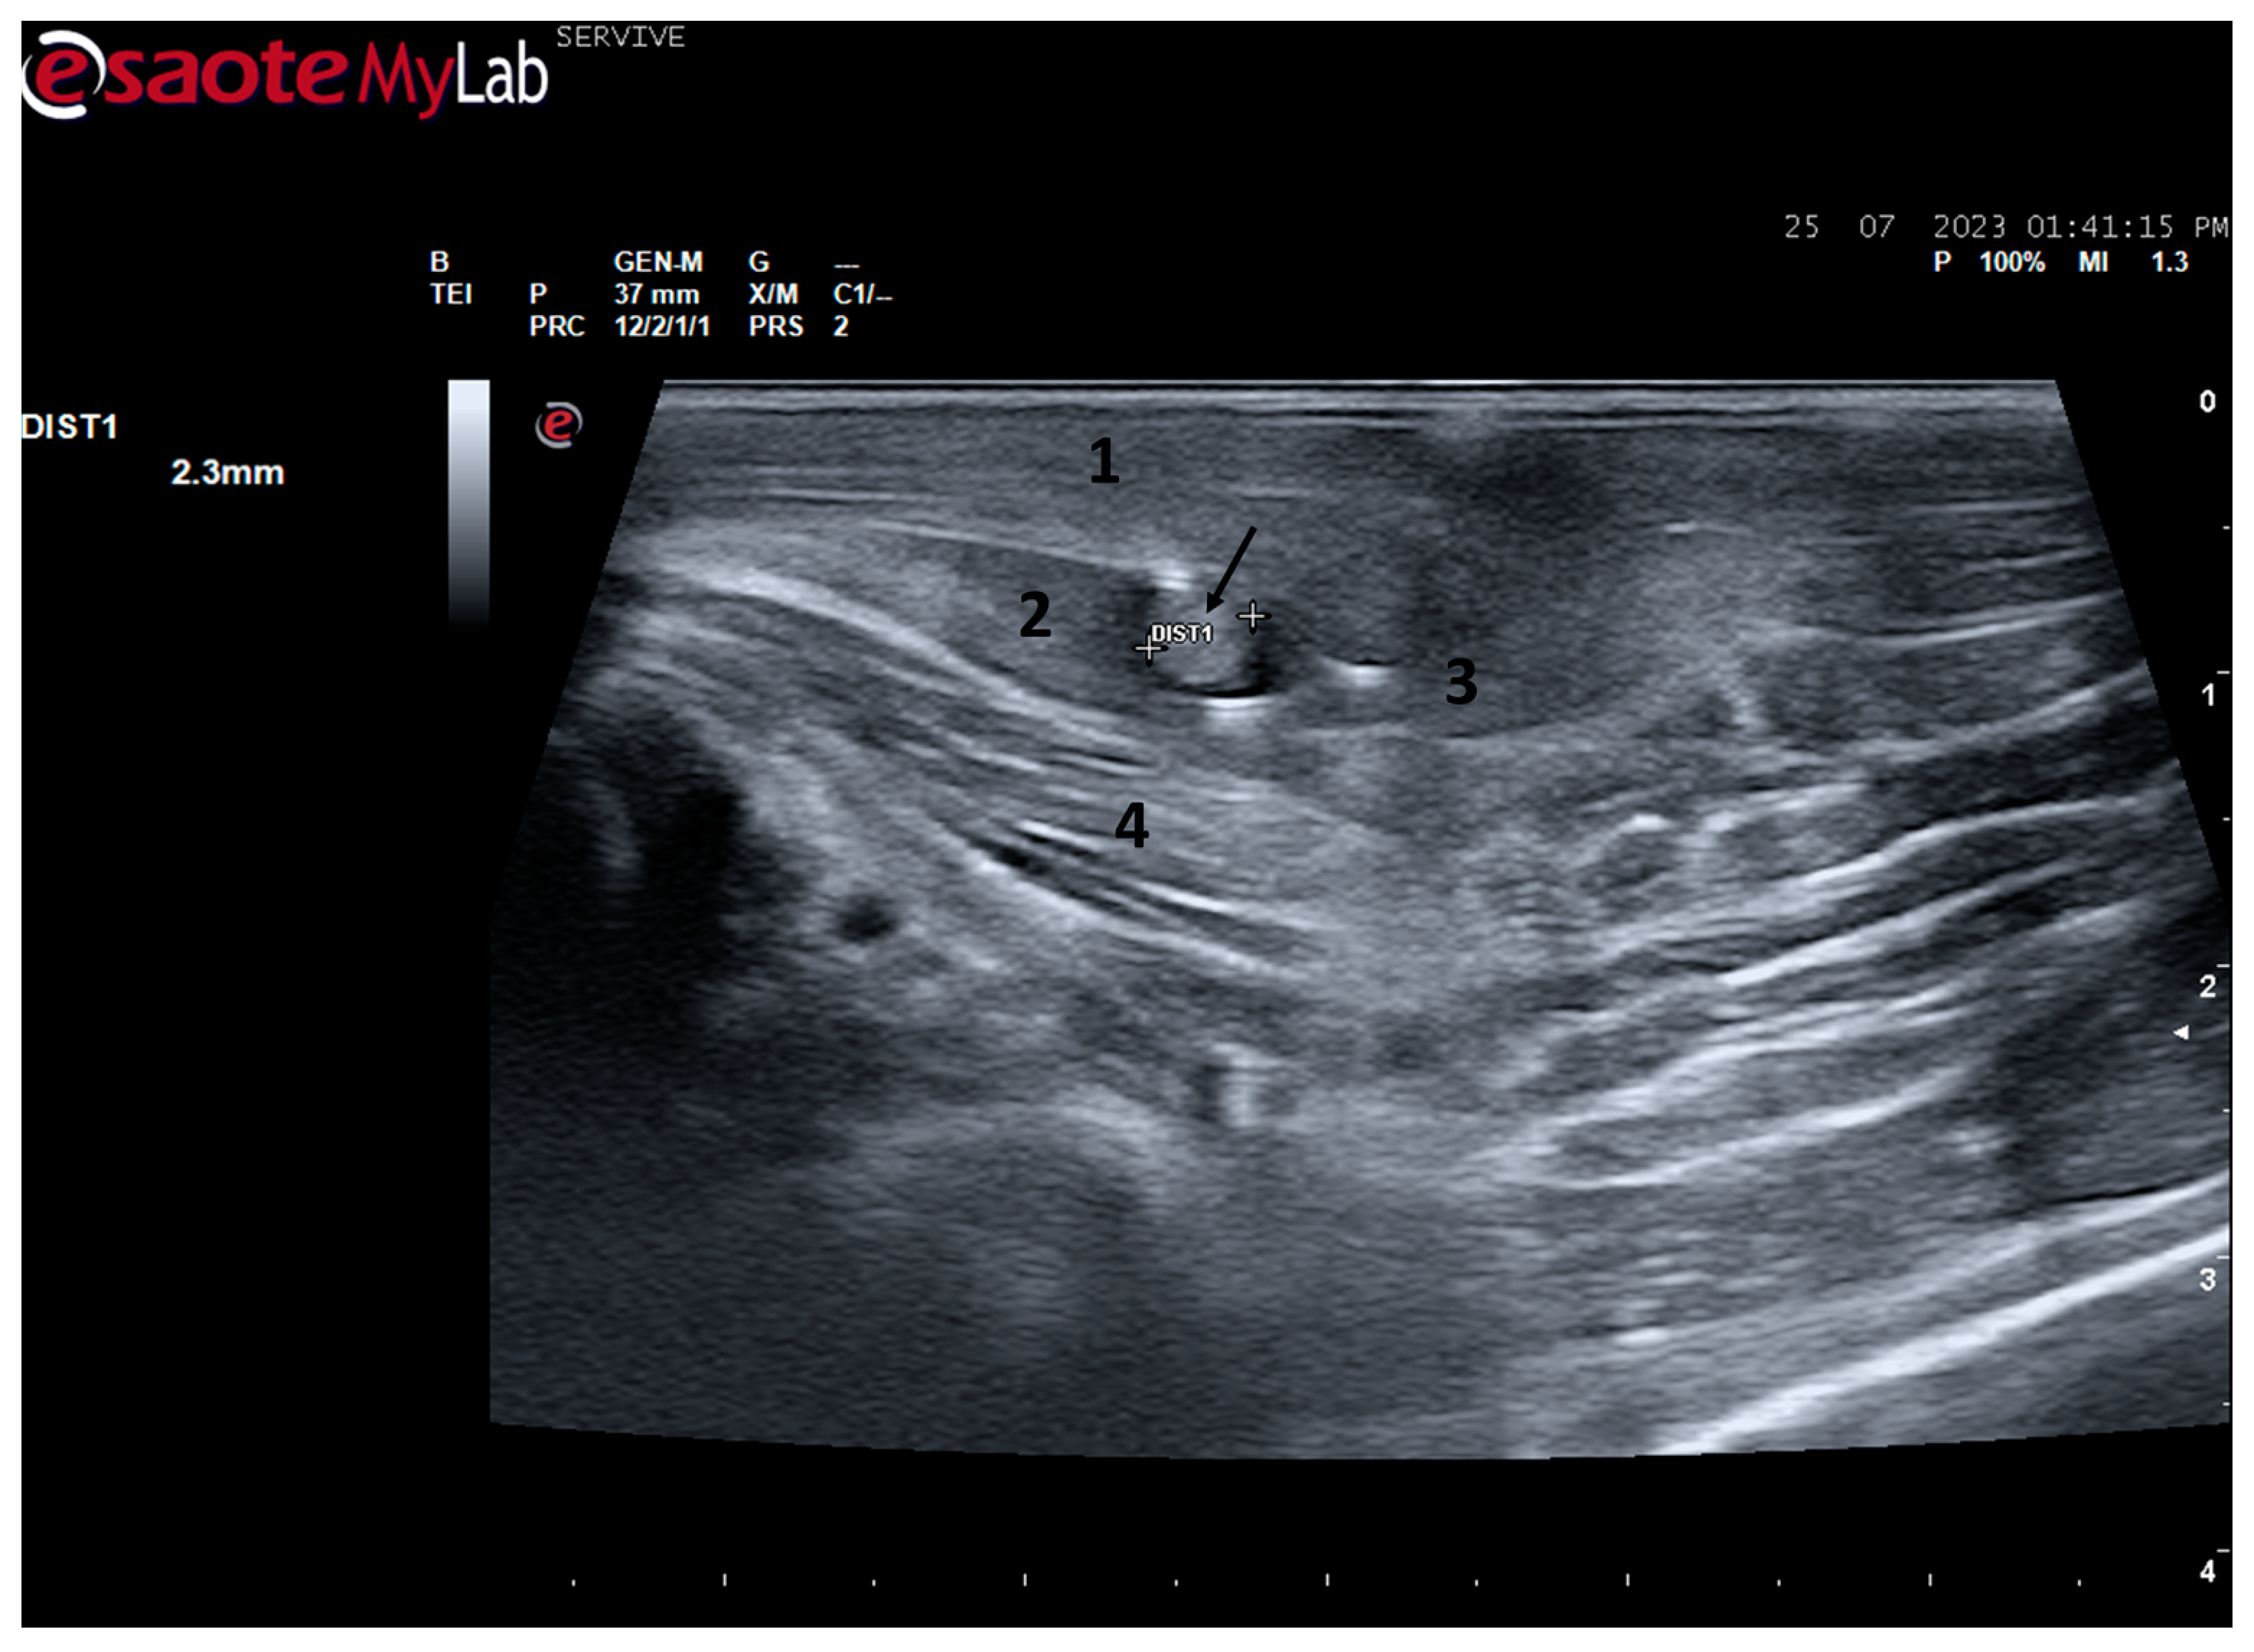

Figure 8.

Ultrasound image of the left sciatic nerve before its branching site, cross section (black arrow). In this plane, the nerve appears as an echogenic tubular structure surrounded by the musculature of the region. (1) Biceps femoris muscle; (2) vastus lateralis muscle; (3) Semitendinosus muscle (4) adductor muscles. DIST1 represents the measurement of the diameter of the sciatic nerve before its branching site.